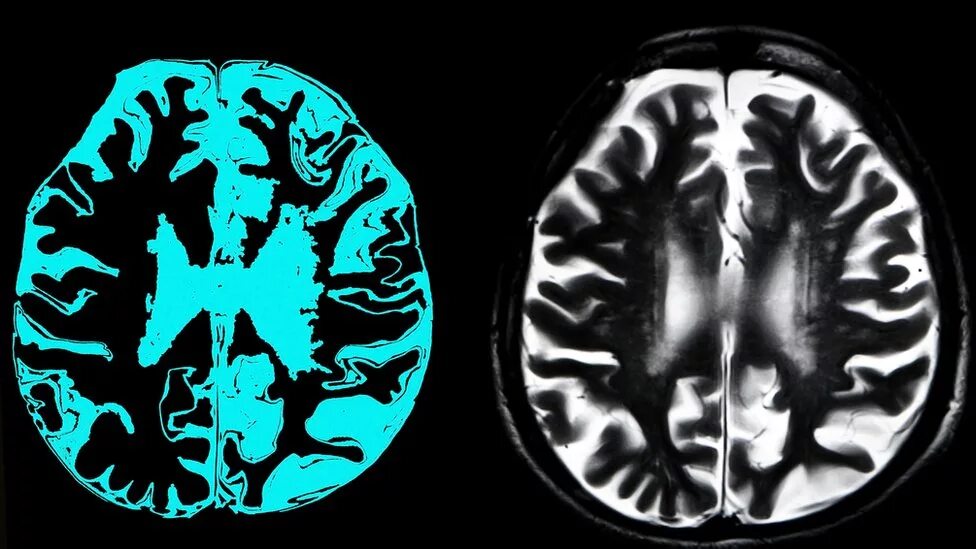

Мозг при деменции